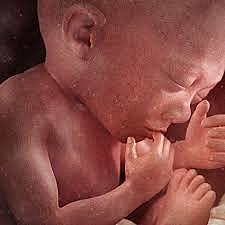

• Semana 32

Semana 32

Su cabeza está proporcionada con respecto al resto del cuerpo.

Las uñas han completado su desarrollo y si es un chico sus testículos ya se encuentran dentro de la bolsa escrotal.